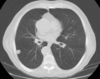

Imagen de TC de alta resolución que muestra fibrosis pulmonar.

Principales utilidades de TC de alta resolución son:

• Valorar el grado de afectación de enfermedades intersticiales pulmonares.

• En pacientes EPOC, para valorar el grado de enfisema y pequeñas zonas de atrapamiento aéreo.

• Determinar la gravedad y extensión de bronquiectasias.

• Valorar qué área es más rentable biopsiar.